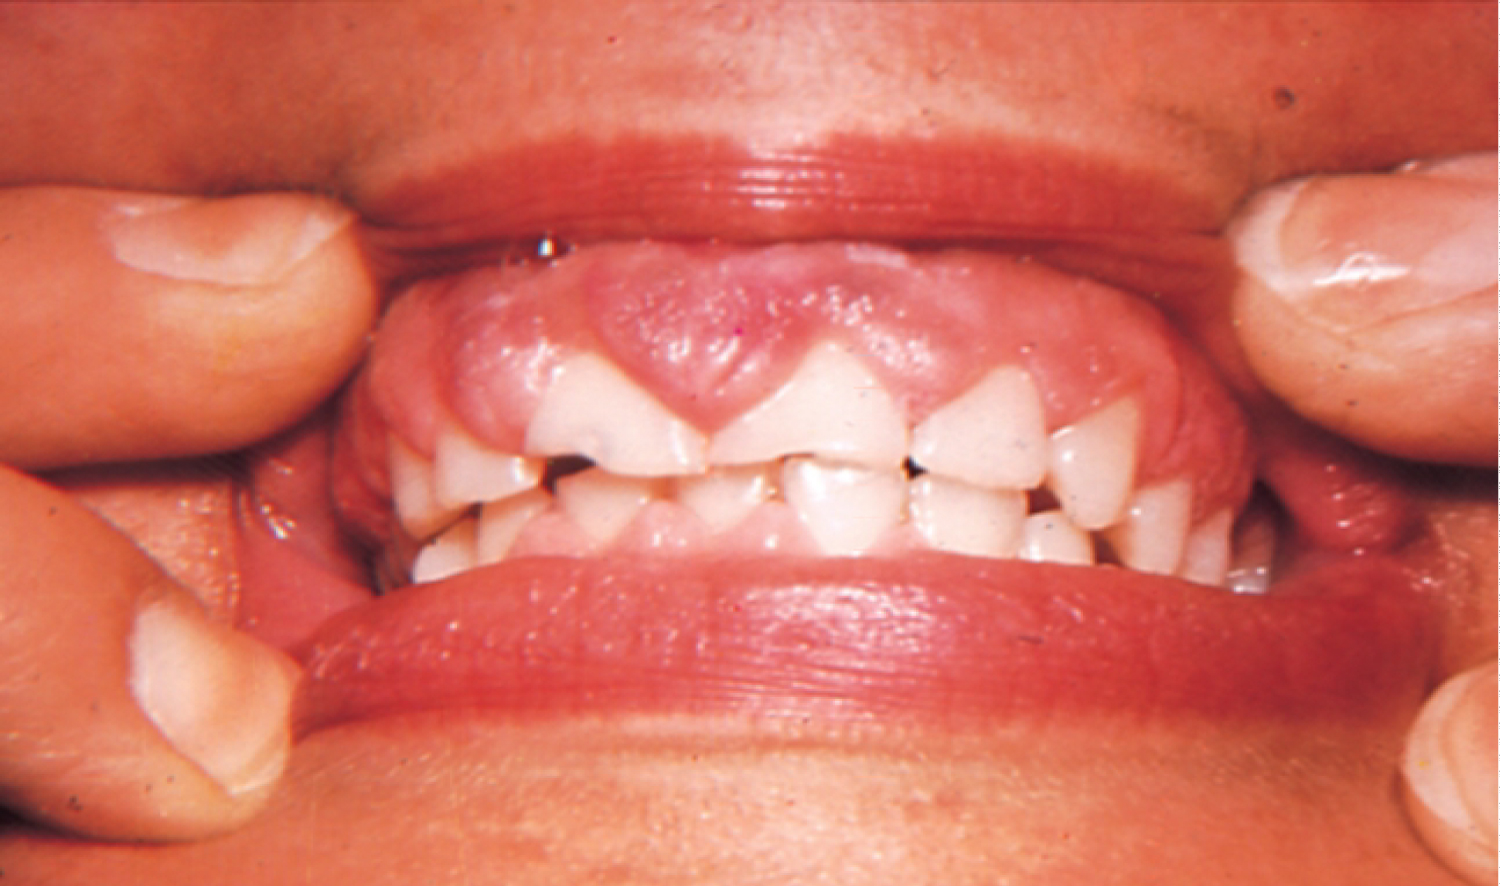

Phenytoin

Phenytoin is an anticonvulsant medication. It has been in use for about 80 years and it remains the main agent for the treatment of epilepsy up to this day, as well as being a useful agent in case of cardiac arrhythmias and several neuralgias [1]. It has been reported that 50% of Phenytoin recipients experience gingival hyperplasia. An even higher percentage is recorded among adolescents. The enlargement of the gingiva usually becomes noticeable within three months after the beginning of the treatment. In most cases, gingival hyperplasia caused by Phenytoin is not resolved with the cessation of treatment [2]. Hyperplastic gingiva as a result of Phenytoin usage can be seen in Figure 2. It has been suggested that the mechanism in which Phenytoin causes gingival overgrowth is by mast-cell mediated androgen stimulation of gingival fibroblasts. As a result of androgen stimulation, further expression of the enzyme 5α-reductase takes place within the cells. Findings of a study investigating the mechanisms of phenytoin-induced gingival hyperplasia have suggested that these responses, which take place in gingival fibroblasts, could be a reason to gingival enlargement [9].

Figure 2: Gingival hyperplasia caused by phenytoin. View Figure 2